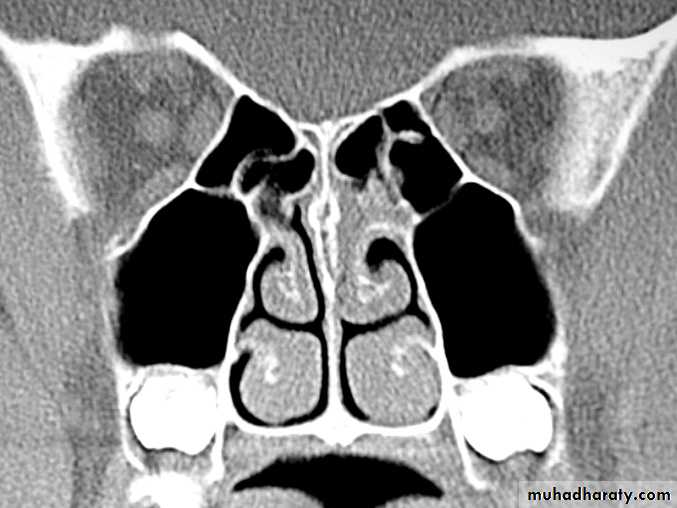

.permanent hypertrophic changes accompany the inflammatory oedema and cellular infiltration in all the constituent parts of the mucosa i.e. stroma , glands , blood vessels , and lymphatic tissue . the epithelium loses clilia and shows a tendency to squamous metaplasia . the mucosa becomes thick and nodular , especially at the extremities and free border of the the occupy the posterior choana . fibrosis can cause venous and lymphatic obstruction . if the resulting passive edema occurs in the situation where the mucosal stroma is loose , polypi form . nasal polyposis , however , usually indicate an allergic or vasomotor origin of the rhinitis , in which the polyposis results from increases capillary permeability

As for simple chronic rhinitis , with the addition of limited reduction of the hypertrophied inferior turbinate and removal of any polypi . topical decongestant preparation must be discouraged or discontinued . reduction is achieved by :